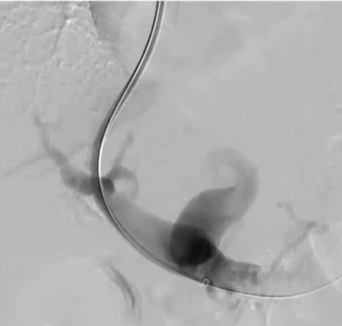

栓塞材料的可及性(例如病灶栓塞材料的可到达性)accessability (e.g. reachability of the nidus) 栓塞的预期深度intended deepness of embolization 如果需要让栓塞填满最后1mm 预期效果(例如:门静脉栓塞的炎症)intended effect (e.g. inflammation in PVE) 凝血状态(达到止血效果所需的时间)coagulation state (duration until hemostasis) 并发症(过敏、心律不齐、肺动脉高压、肝纤维化等)comorbidities (allergies, arrythmia, pulmonary hypertension, lung fibrosis etc.) 处于危险中的结构(包括下游部分-downstream和反流部分) structures at risk (downstream & backwash) 靶病变定位(浅层与深层) target lesion localization (superficial vs. deep) 不会选择一些会引起炎症的东西,因为那会病人来说真的很痛苦浅层病变 栓塞所需的速度(例如:危及生命的出血情况)required speed of embolization (e.g. life threatening hemorraghe) 院外专业人员(DSA技术人员和介入放射科医生)local expertise (technicians & IR's) 可用性与定价 availabilty & pricing Patient assessment for the choice of the ideal liquid emboli 影像学 62岁 男性